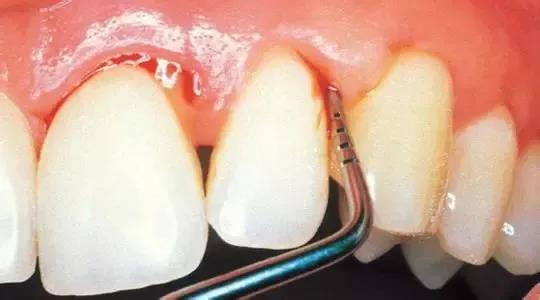

2.日常的维护措施:

使用含氟的牙膏刷牙,在诊所接受牙齿涂氟的处理可以增强牙齿抵抗蛀牙的能力。同时,良好的卫生习惯也是必须的,运用正确有效的刷牙方法每天刷牙至少2次,饭后用牙线清除牙缝间的食物残渣,每年到口腔诊所检查和洁牙1~2次可以有效的维护口腔健康。